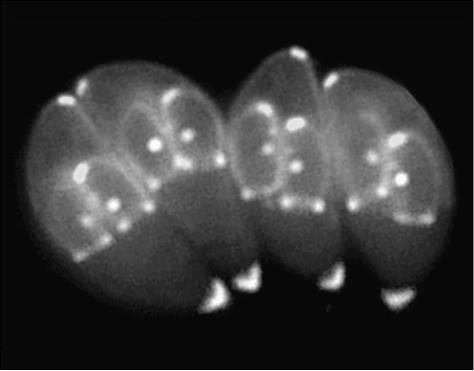

Иллюстрация к книге — 100 великих тайн медицины [i_066.jpg]

Toxoplasma – один из наиболее распространенных человеческих паразитов

Дело в том, что Toxoplasma – один из наиболее распространенных человеческих паразитов. Им инфицированы от 30 до 60 процентов населения земного шара. А виноваты в том… кошки – домашние любимицы многих.